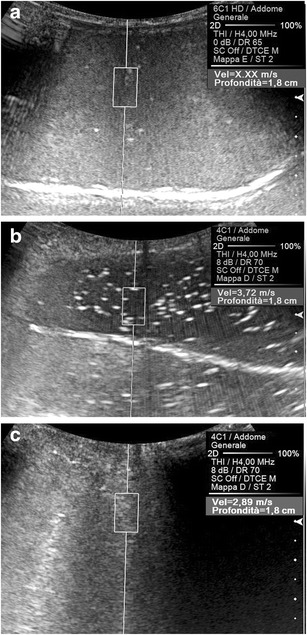

Fig. 2.

Effect of the elasticity of the target on the speed of propagation of the shear waves. Shear waves do not generate (SWV not measurable: “X.XX”) in pure water (a) and travel quite fast (3.72 m/s) in oil (b). In a water-oil emulsion (c) the SWV (2.89 m/s) is lower than in pure oil

Fig. 4.

Effect of the compression on the speed of propagation of the shear waves. Longitudinal US scans on the left lobe of the liver in a healthy subject. A lower SWV value (1.18 vs. 1.52 m/s) is measured, exerting on the transducer a mild (a) rather than a strong (b) manual compression